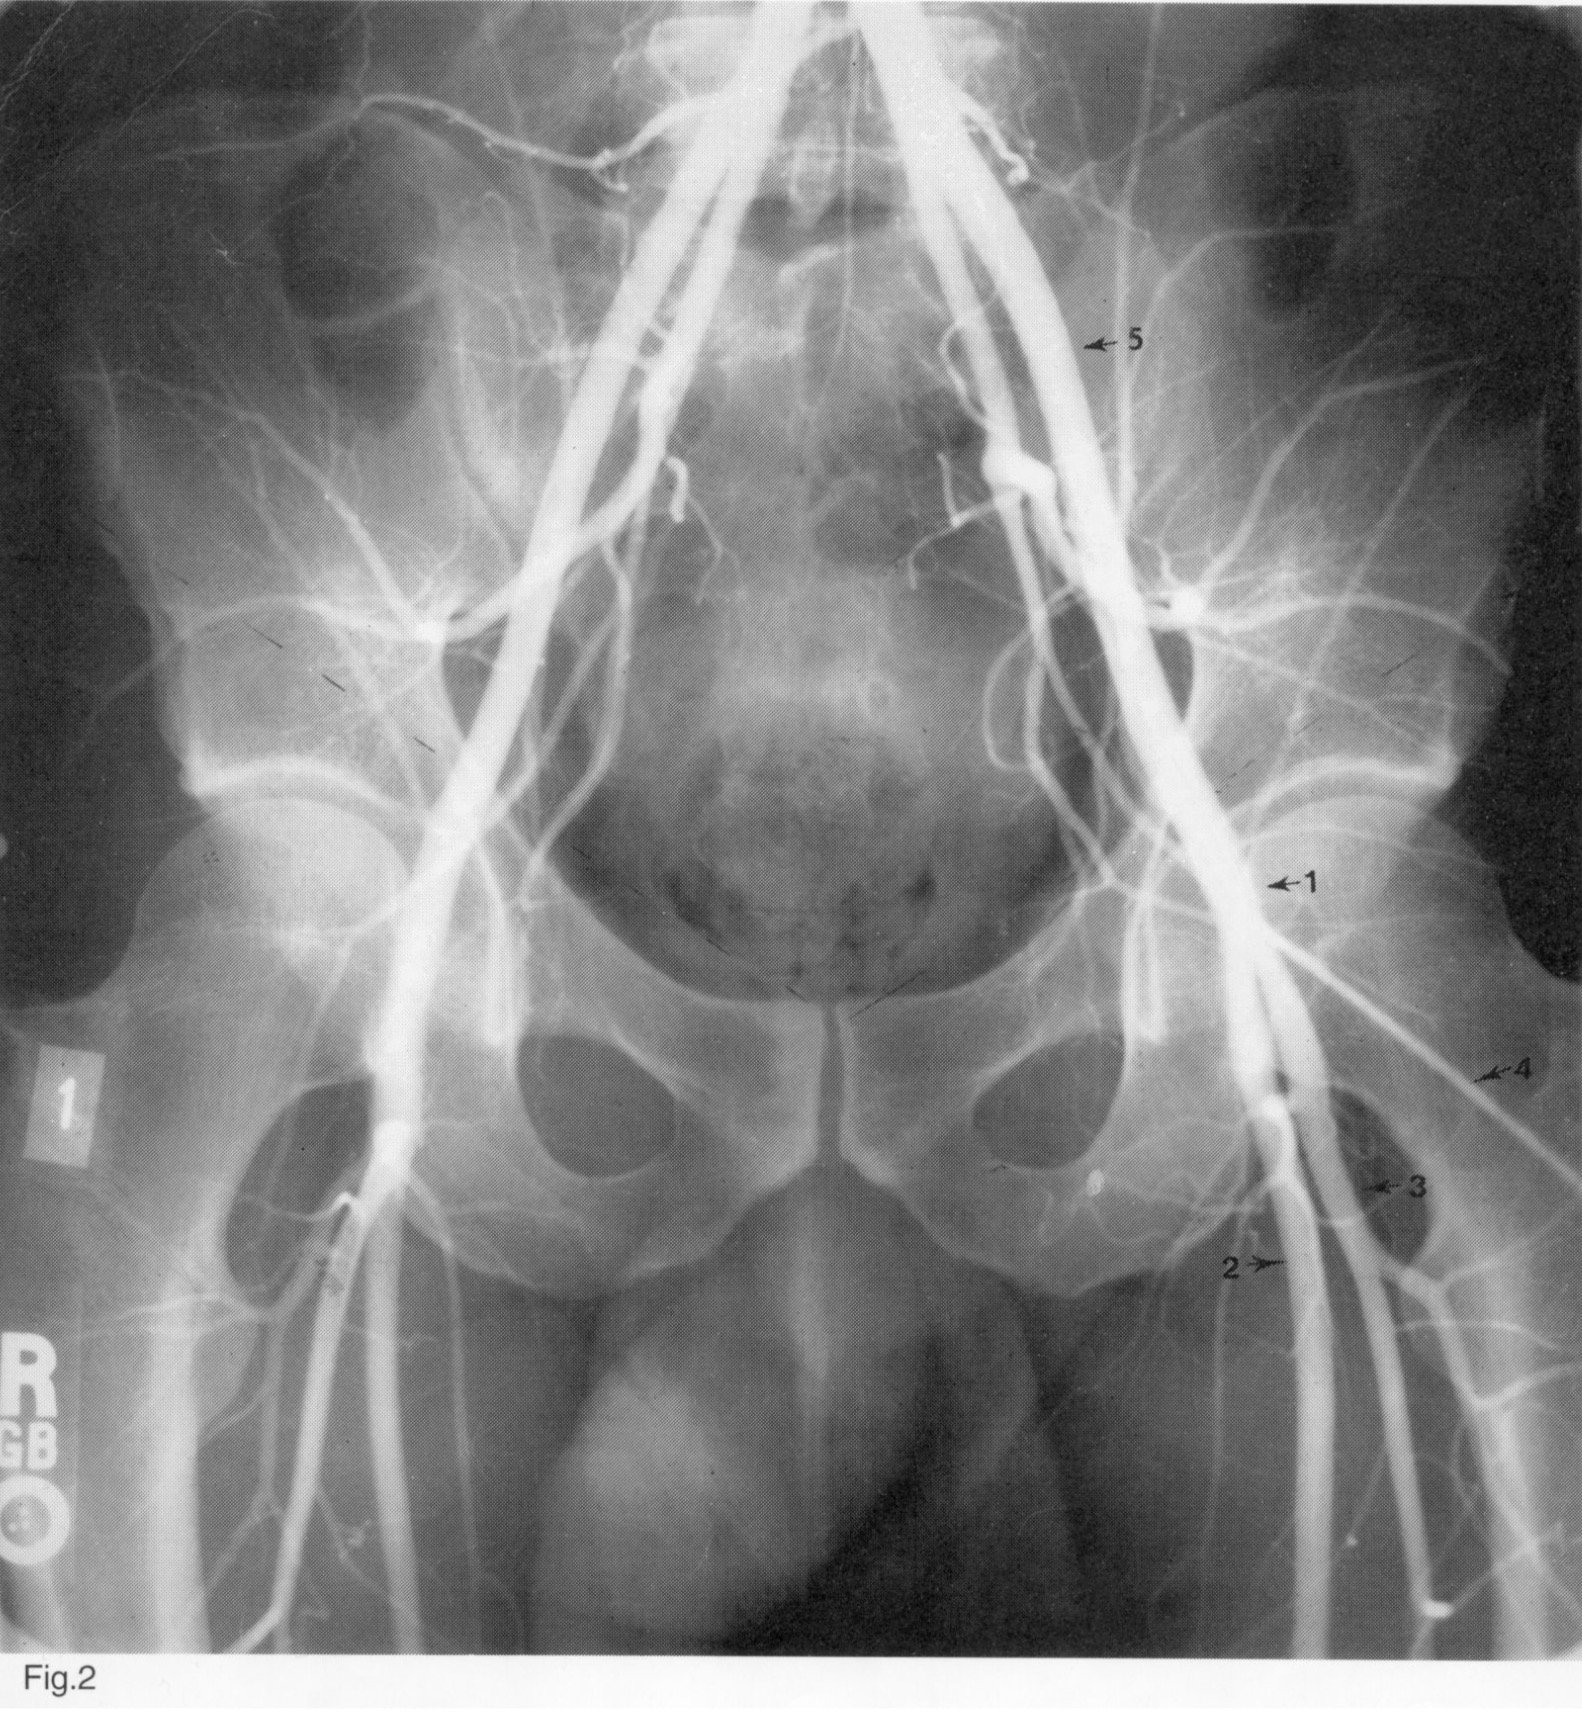

1

A. femoralis communis

2

A. femoralis superficialis

3

A. profunda femoris

4

Kateteris

5

A. iliaca externa